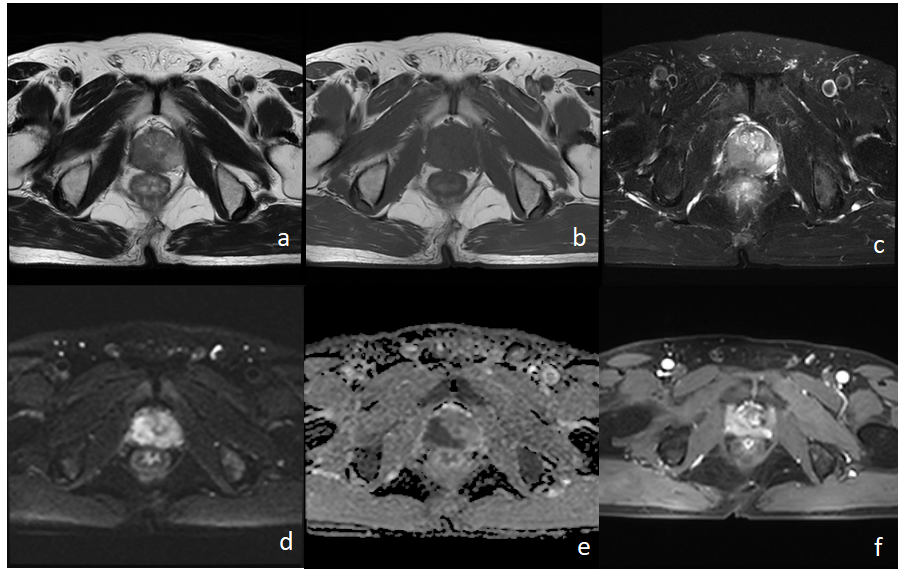

近日,我院放射科新开展了一例盆腔MRI扫描——前列腺MR扫描,下面我们来看看这个例子吧。

患者男72岁 反复肛门部坠胀、便不尽感3+月。

4月6-7日 前列腺MRI

a-c:前列腺右侧份(以外周带为主)T1WI斑片状等低信号影,T2WI低信号影

d-e:病灶DWI上呈高信号,ADC上呈低信号(弥散受限)

f:增强扫描病灶明显强化

1. 患者肿瘤标志物(PSA↑)异常,提示前列腺有问题,建议做MRI。

2. 常规MRI示前列腺右侧份斑片灶,DWI示病灶弥散受限,增强扫描病灶明显强化,提示前列腺Ca可能(需与慢性前列腺炎鉴别).